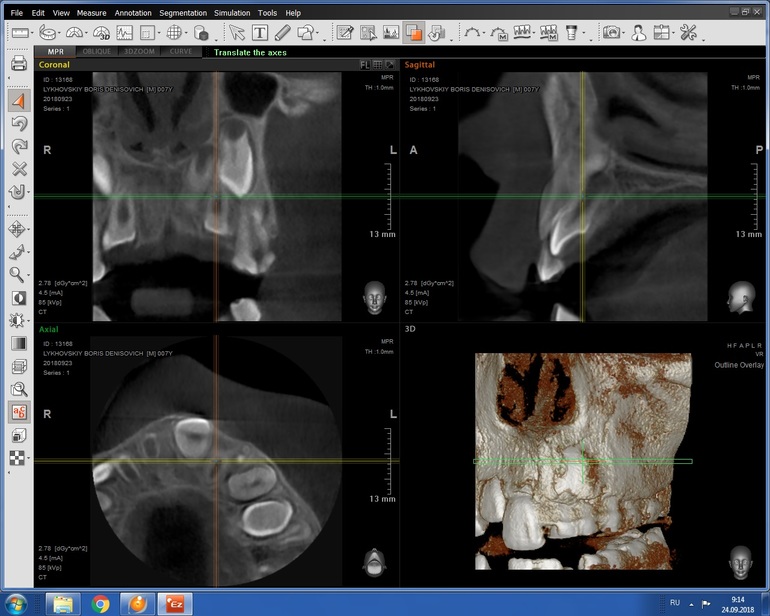

Здравствуйте! Сделали КТ,не с первого раза и не со второго, увы. Поэтому у врача еще небыли. А Вы по КТ сможете подсказать,что у нас и к чему готовиться? Была бы очень признательна!

Я прочитала, КТ всегда делается, если есть подозрение на сверхкомплектные зубы. Без КТ никто в челюсть не полезет удалять что-то. Про брекеты нам никто не говорил, Анна :)

Спасибо, наверное стоит съездить. Насчёт КТ - Вы не поняли, его нужно сделать чтобы подтвердить наличие сверхкомплектные зубов и то, насколько они мешают коренному. Именно на основании КТ принимают решение об удалении сверхкомплектных.

КТ это обязательно при сверхкомплектах, далее решают ортодонт и хирург какими методами и как их убирать. Бывает вытягивают брекетами , бывает убирает хирург, но когда , в каком возрасте это делать будет ясно по КТ.